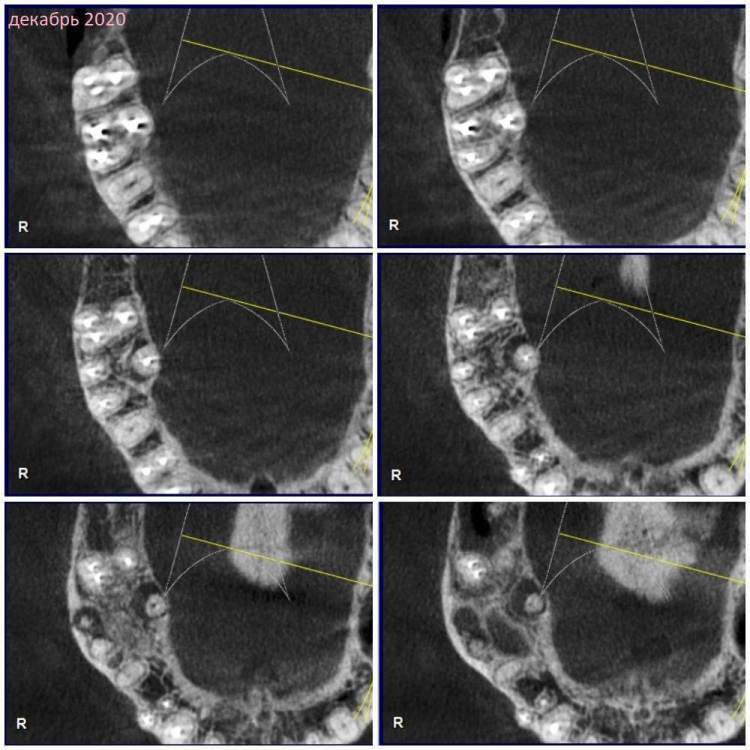

Зуб 17.

КТ наскринила парочку. Если нужно будет более подробно – выложу еще.

Декабрь 2020